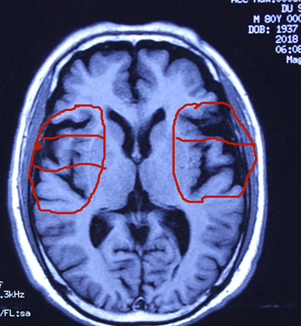

杜先生阿尔茨海默症典型病例治愈简介: 2018年8月30日接诊。接诊地点:北京石景山八大处中西医结合医院贾学铭教授诊室。 患者:杜先生,男,80岁,经常头晕不舒10余年,近二年多病情加重,出现记忆障碍渐渐加重,对事情过后即忘,每天早上下楼买去3-4次买同一种报纸,买后放下过会又去买,别人让他不要买了,过后又去买回来了,对其他刚刚放下的物品回头即忘,对其他人的名字或数字经常记不清等,经北京多家大医院诊断为:阿尔茨海默症,经过多种方法治疗无效。从网上查到而来要求治疗,自带北京世纪坛医院核磁共振2018年8月29日片显示:脑萎缩(严重)。接诊后给以纯中药治疗4个多月,头晕不舒消失,记忆恢复正常,还能很正常的照顾他人,症状全部消失。2019年1月2日又到北京世纪坛医院作核磁共振片显示:脑萎缩与前片比较明显恢复。治疗结果:阿尔茨海默症完全治愈。以下是核磁共振片治疗前后的对比: 杜先生阿尔茨海默症治愈前后拍核磁共振片比较,要观察细节:

2018年8月29日前见片治疗脑萎缩严重。病情严重。 2019年1月2日治疗后见片脑萎缩减轻。病情治愈。

2018年8月29日前见片治疗脑萎缩严重。病情严重。 2019年1月2日治疗后见片脑萎缩减轻。病情治愈。 脑组织逆生长的情况见左右两个图内红圈相对等部位的比较,圈内白色的部分是脑组织,圈内黑色的部分是没有脑组织了是萎缩后空缺的现象,黑色越多脑萎缩越严重,白色越多脑组织越多,脑组织多了,就是改变了脑萎缩,就是脑组织逆生长,因此,通过中药使脑组织逆生长就消除了和治愈了脑部的疑难病。该患者的阿尔茨海默症通过纯中药达到了脑组织逆生长,患者的记忆障碍就正常了,病情就治愈了。 实践证明阿尔阿尔茨海默症的发病,不仅是现代医学认为的海马体萎缩的问题,是脑部整体出现了问题,也不是不可治愈的疾病,是能够治愈的。我们经过几十年的研究探讨创新,用纯中药治愈阿尔茨海默症是科学的真实有效的,是现实的!只要是脑组织逆生长,阿尔茨海默症就必然能够治愈。